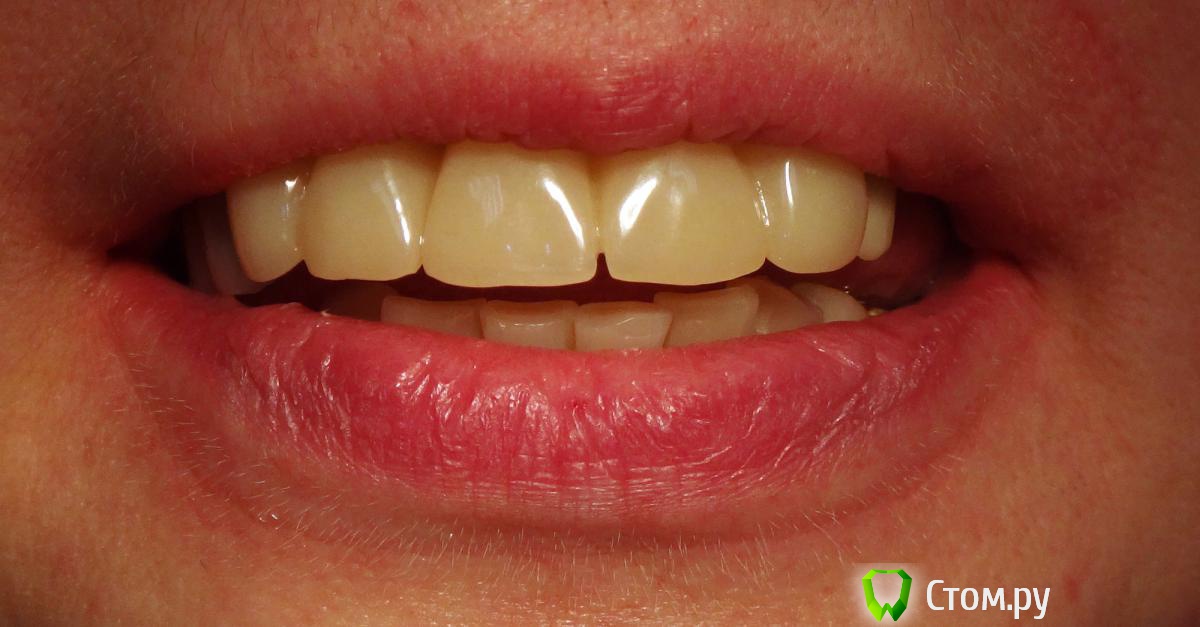

Kalipso Опубликовано 28 августа, 2014 Поделиться Опубликовано 28 августа, 2014 Я ставлю сразу после удаления .1 . Снимаю слепок до удаления , и прошу техника либо сделать коронку или wax up после чего по ключу сама изготавливаю .2. Удаляю .3.Жидкотекучим креплю коронку . Как- то так . Это наверно самая моя первая такая работа .http://s017.radikal.ru/i432/1408/7c/d61e22c1c7ae.jpg http://s018.radikal.ru/i519/1408/d2/23c0aebcd1b4.jpg http://s016.radikal.ru/i336/1408/51/3ede7c77a5d0.jpg http://s41.radikal.ru/i091/1408/cc/604419754cb7.jpg 3 Ссылка на комментарий

Kalipso Опубликовано 5 сентября, 2014 Поделиться Опубликовано 5 сентября, 2014 Мне кажется или зениты у двоек будут разной высоты? Что делать если после удаления десна выше зенитов соседних? Получается если поставить времянку сразу же и ограничить десну , то овоид получится выше чем надо. Если подождать после удаления несколько дней, опустится ли десна?Именно в этом случае в дальнейшем планировалось хир. удлинение .Если вы хотите сохранить овойд делайте временную конструкцию одномоментно с удаление , если найду покажу фото где пациент пришел на третий день после вид совершенно другой . Ссылка на комментарий

Slaggy Опубликовано 15 сентября, 2014 Поделиться Опубликовано 15 сентября, 2014 тут прикус будете поднимать?просто по фото 13 в контакте с антагонистом или мне кажется? Есть ответ про 13 Прошел месяц: Ссылка на комментарий